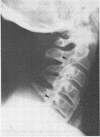

This report describes a patient presenting with a spastic quadriplegia who was found to have both diffuse idiopathic skeletal hyperostosis (DISH) and ossification of the posterior longitudinal ligament (OPLL) in the cervical spine. There was a dramatic worsening of his symptoms during a myelogram examination of the neck. It is suggested that computed tomographic imaging of the neck is the preferred investigative procedure if OPLL is suspected as a cause of cervical myelopathy.